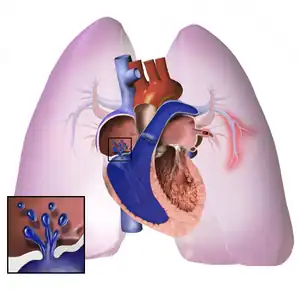

O processo subjacente da hipertensão pulmonar varia e, com frequência, múltiplos fatores são responsáveis. Normalmente, o leito vascular pulmonar pode receber o volume sanguíneo liberado pelo ventrículo direito. Ele apresenta uma baixa resistência ao fluxo sanguíneo aumentado por meio da dilatação dos vasos na circulação pulmonar. Entretanto, se o leito vascular pulmonar está destruído ou obstruído, como na hipertensão pulmonar, a capacidade de receber qualquer fluxo ou volume do sangue fica prejudicada, e, então, o fluxo sanguíneo aumentado eleva a pressão da artéria pulmonar. À medida que a pressão da arterial pulmonar aumenta, também aumenta a resistência vascular pulmonar. A constrição da artéria pulmonar (como na hipoxemia ou hipercapnia) e a redução no leito vascular pulmonar (que ocorre com a embolia pulmonar) resultam em um aumento na resistência e pressão vasculares pulmonares. Essa carga de trabalho aumentada afeta a função ventricular direita. Por fim, o miocárdio não consegue satisfazer as demandas crescentes impostas a ele, levando à hipertrofia (aumento e dilatação) e insuficiência ventricular direita.